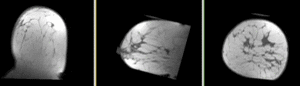

this is the fixed reference image. All images are aligned into this space lleft this is the DTI Baseline scan, to be registered with the T2

fixed image/target

pre Rx MRI

moving image

post Rx MRI